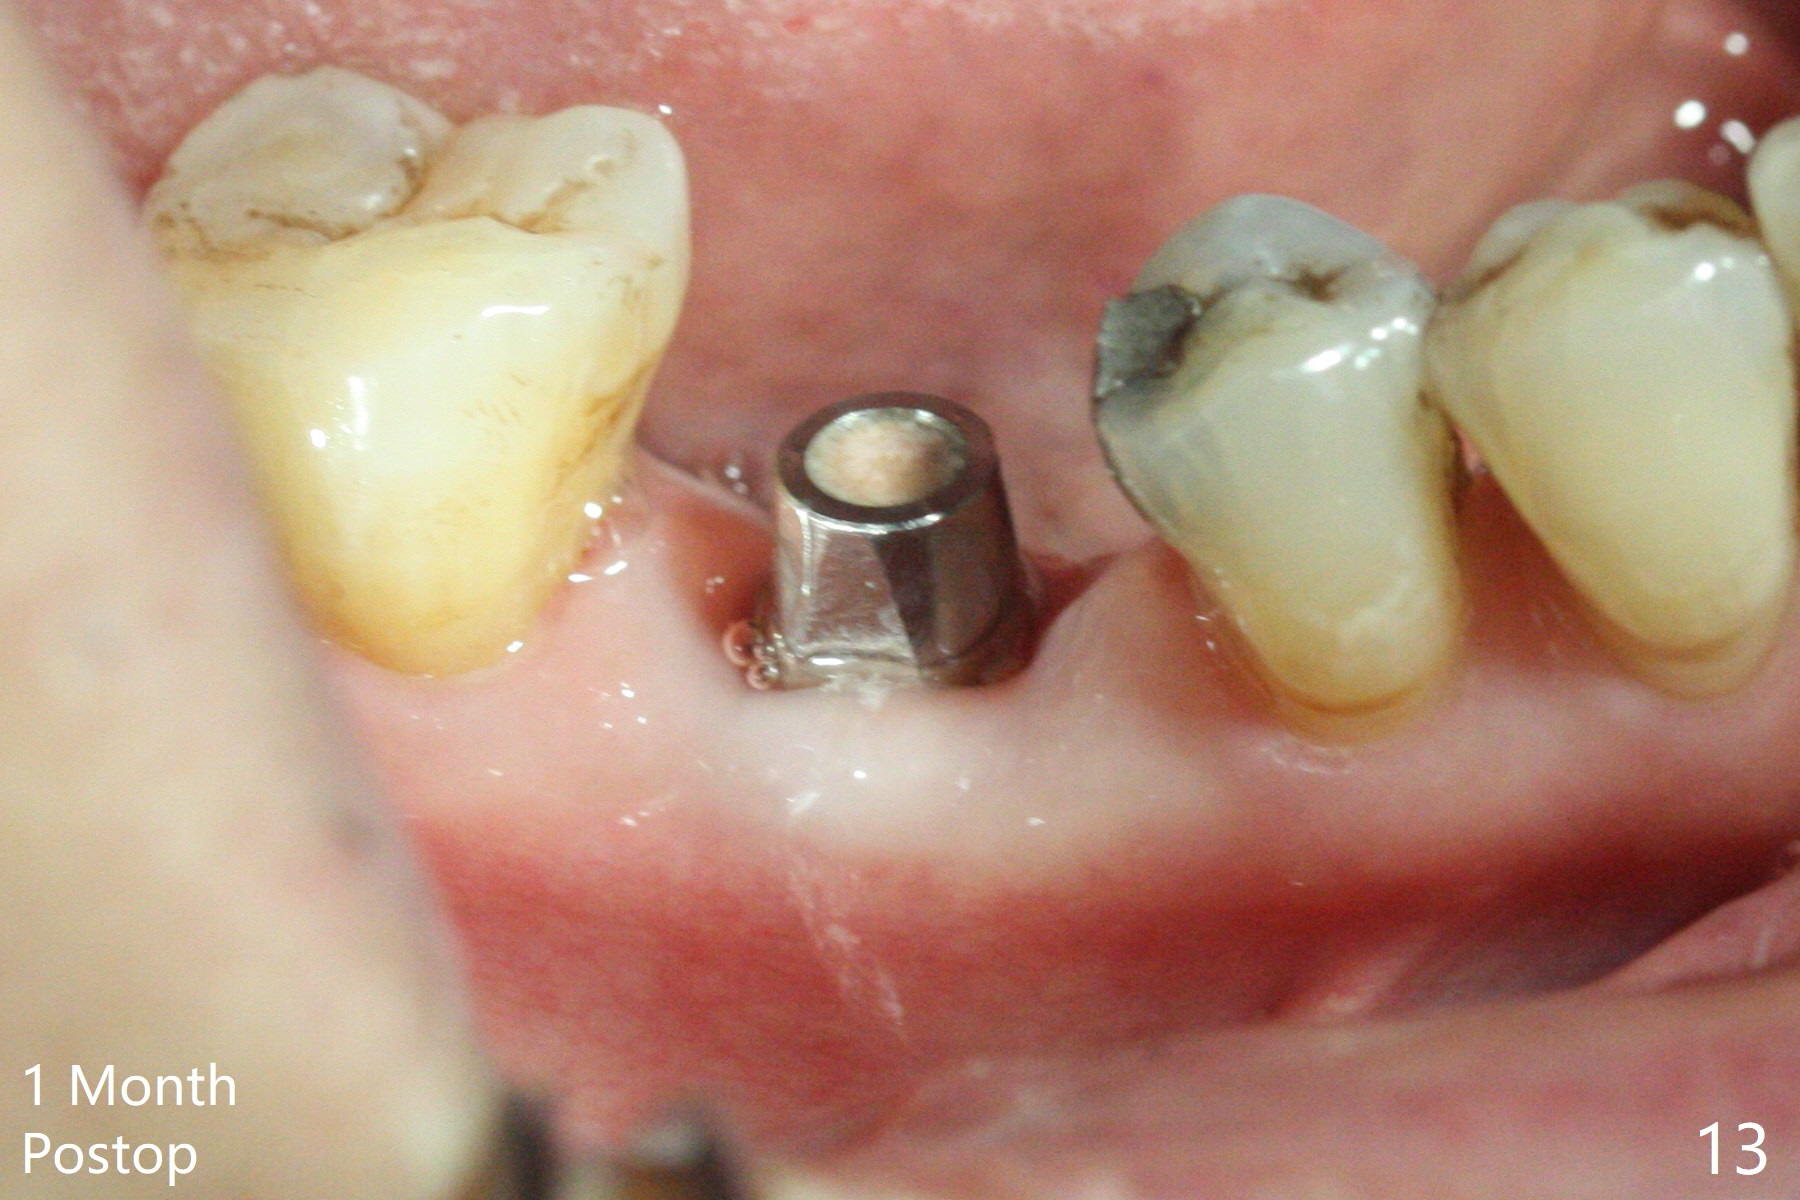

As planned, the crown of the tooth #30 with lingual (Fig.1 L) caries is removed and flattened with surgical handpiece so that the guide is able to be seated without interference. The osteotomy by 10.5 mm offset bone trimmer is lingual (Fig.2 white circle; due to in part the lingual caries and in part design error); in order to let the osteotomy to bounce back buccal, the part of the buccal roots are removed by surgical bur (arrows). The initial osteotomy by 2.2 mm drill is in the middle of the septum (Fig.3). After the last drill (3.5x11.5), the remaining roots are easily removed with proximators; a 4x11 mm dummy implant is placed with low stability and supracrestal lingual (Fig.4). Therefore a 4.5x9 mm final implant is placed with low torque. Following 4x11.5 mm drill, the torque increases to 20 Ncm. With insertion of healing screw, sticky bone (Fig.4 *: .5-1 mm cortical/cancellous allograft) is heavily packed around the implant (arrow), which apparently allows removal of the healing screw and placement of a 6x5.7(3) mm pair abutment without loosening the underlying implant. More bone graft is placed (Fig.6), followed by 2 pieces of PRF membranes. Although the implant is slightly buccally placed (Fig.7, due to over-removal of the buccal root, Fig.2 arrows), it is placed in the septum (Fig.8 S). To further compensate for the low implant stability, setting acrylic is applied in the edentulous area, particularly into the undercuts of the neighboring teeth (Fig.9 *) and around the abutment. The lingual margin of the acrylic dressing is extended (Fig.10 arrow) to cover the soft tissue defect associated with the lingual caries. As compared to the design (4x10 mm, Fig.11), the implant (4.5x9 mm, Fig.12) is placed buccal and ~ 2 mm deeper, reducing the chance of periimplantitis. The acrylic dressing is in place, but has mobility. The gingiva is healthy 2 weeks postop. The dressing is removed 1 month postop; the socket heals around the abutment buccal (Fig.13) and lingual (Fig.14). In spite of the immediate provisional, the abutment margin is substantially subgingival mesial 4 months postop, extremely difficult to take impression. A smaller diameter and longer cuff abutment is placed (Fig.15). The lingual gingiva heals normal 5 months postop, immediately before cementation (Fig.16).